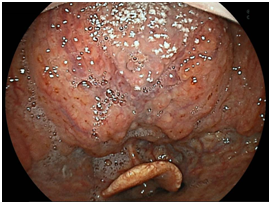

We detected 11 cases of superficial squamous cell carcinoma of the base of the tongue between April 2012 and March 2016. All the patients were complicated with current (n=3) or previous (n=8) esophageal squamous cell carcinoma. The patient characteristics are shown in Table 1. The mean age of the patients was 63.7years (range, 49-73years), and all patients were male. Four cases were diagnosed using trans-nasal endoscopy with the FICE system, seven cases were diagnosed using trans-nasal endoscopy with the LASERIO system. The average time to complete a thorough examination for one patient was approximately from 1 to 2minutes, regardless of the presence of abnormal findings. Biopsy specimen were obtained in all patients, and diagnosed as squamous cell carcinoma pathologically. Table 2 shows the treatment results. Five lesions were flat type (Figure 4A), four were elevated (Figure 4B), and two were depressed (Figure 4C). Regarding the tumor size, eight were T1, three were T2. No lymph node metastasis was detected in any case. Six cases were treated by endoscopic laryngo-pharygeal surgery,15 and 3 cases were treated by chemo-radiotherapy. One case was followed because of esophageal cancer. One case was treated by trans-oral robotic surgery at another hospital. For the seven resected specimens, the median tumor thickness was 800μm (range, 250-3000μm), and the median tumor diameter was 11mm (range, 10-25mm). Histologically, two of these lesions were squamous cell carcinoma in situ, five showed microinvasion of the subepithelial tissue. During a median follow-up period of 26months (range,11-56months), 1 patient, which patient’s tumor thickness was 3000μm, developed lymph node metastasis, which was treated by neck lymphadenectomy and chemo-radiotherapy. Three of the 11 patients cases were died of another disease, and 8 were alive as drafting this manuscript.

Figure 4C Depressed type.

Macroscopic types of superficial squamous cell carcinoma of the base of the tongue.